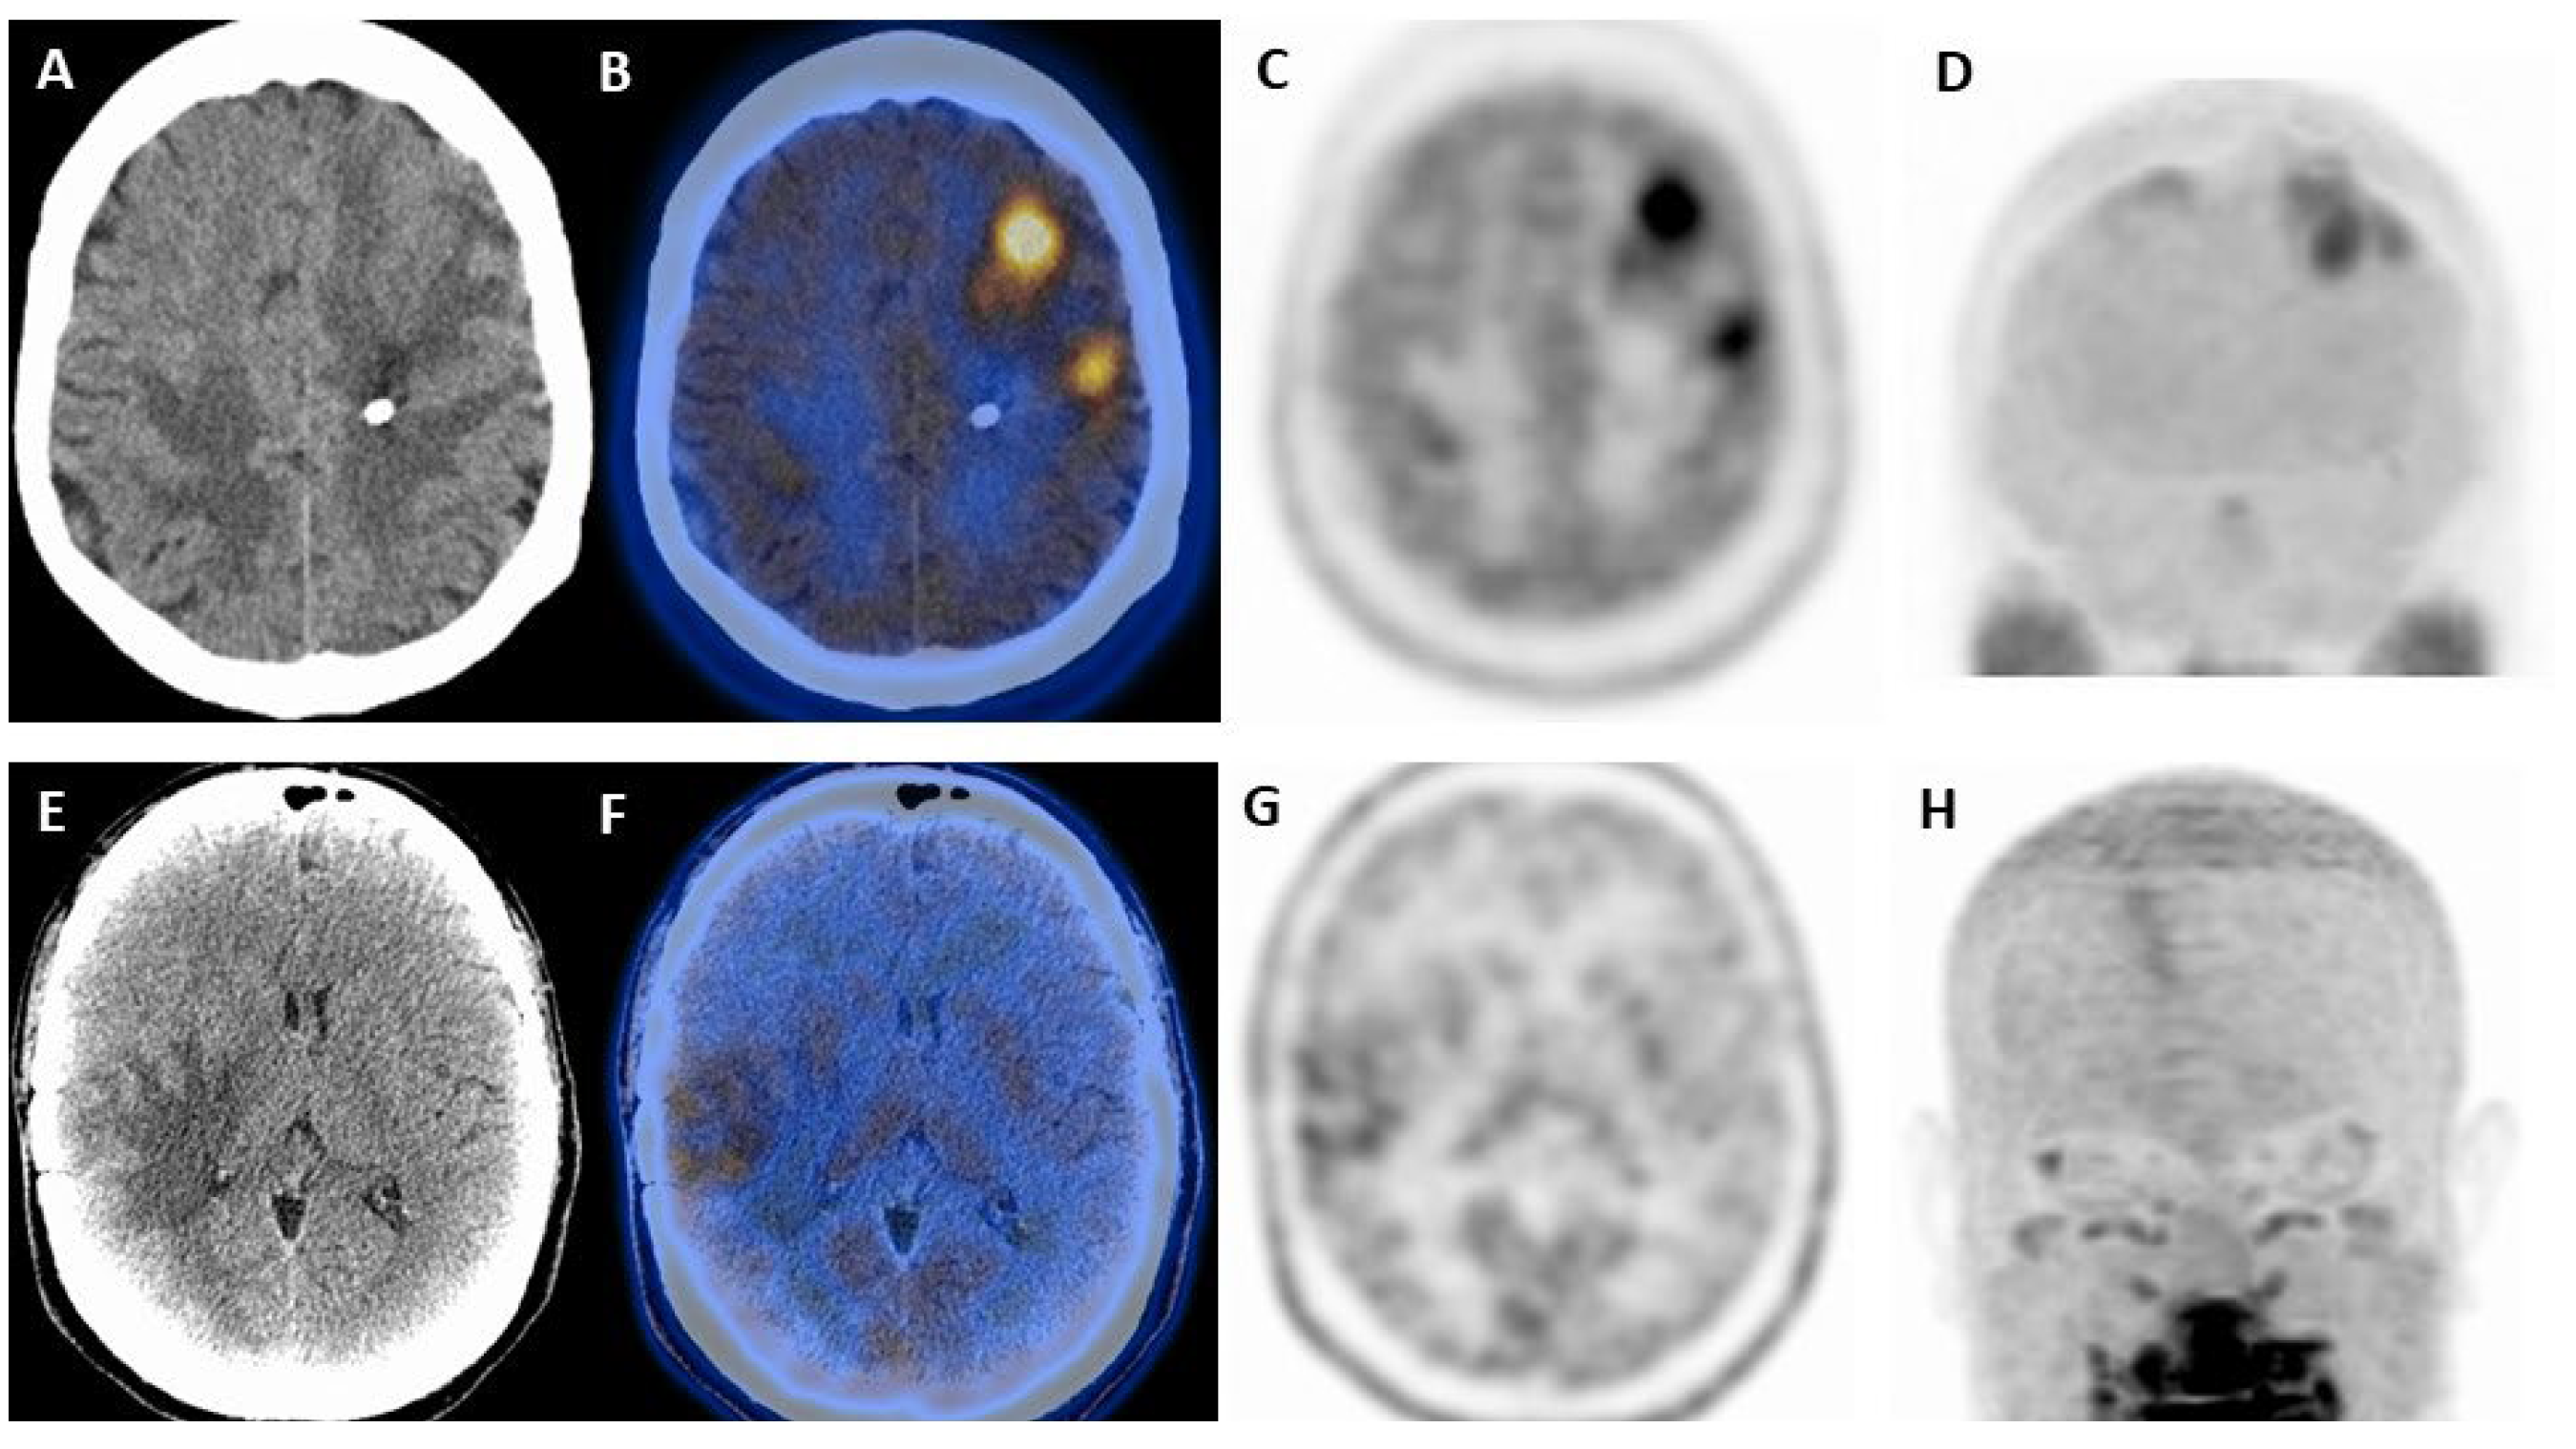

- Horky, L.L.; Hsiao, E.M.; Weiss, S.E.; Drappatz, J.; Gerbaudo, V.H. Dual Phase FDG-PET Imaging of Brain Metastases Provides Superior Assessment of Recurrence versus Post-Treatment Necrosis. J. Neurooncol. 2011, 103, 137–146. [Google Scholar] [CrossRef]

| Horky et al. [27] | 2011 | R | Solid neoplasms | 32 (10/22) | Dual phase PET/CT to differentiate recurrence from radionecrosis | Variation of L/GM > 0.19 between early and delayed: Sensitivity 955% Specificity 100% Accuracy 96% |